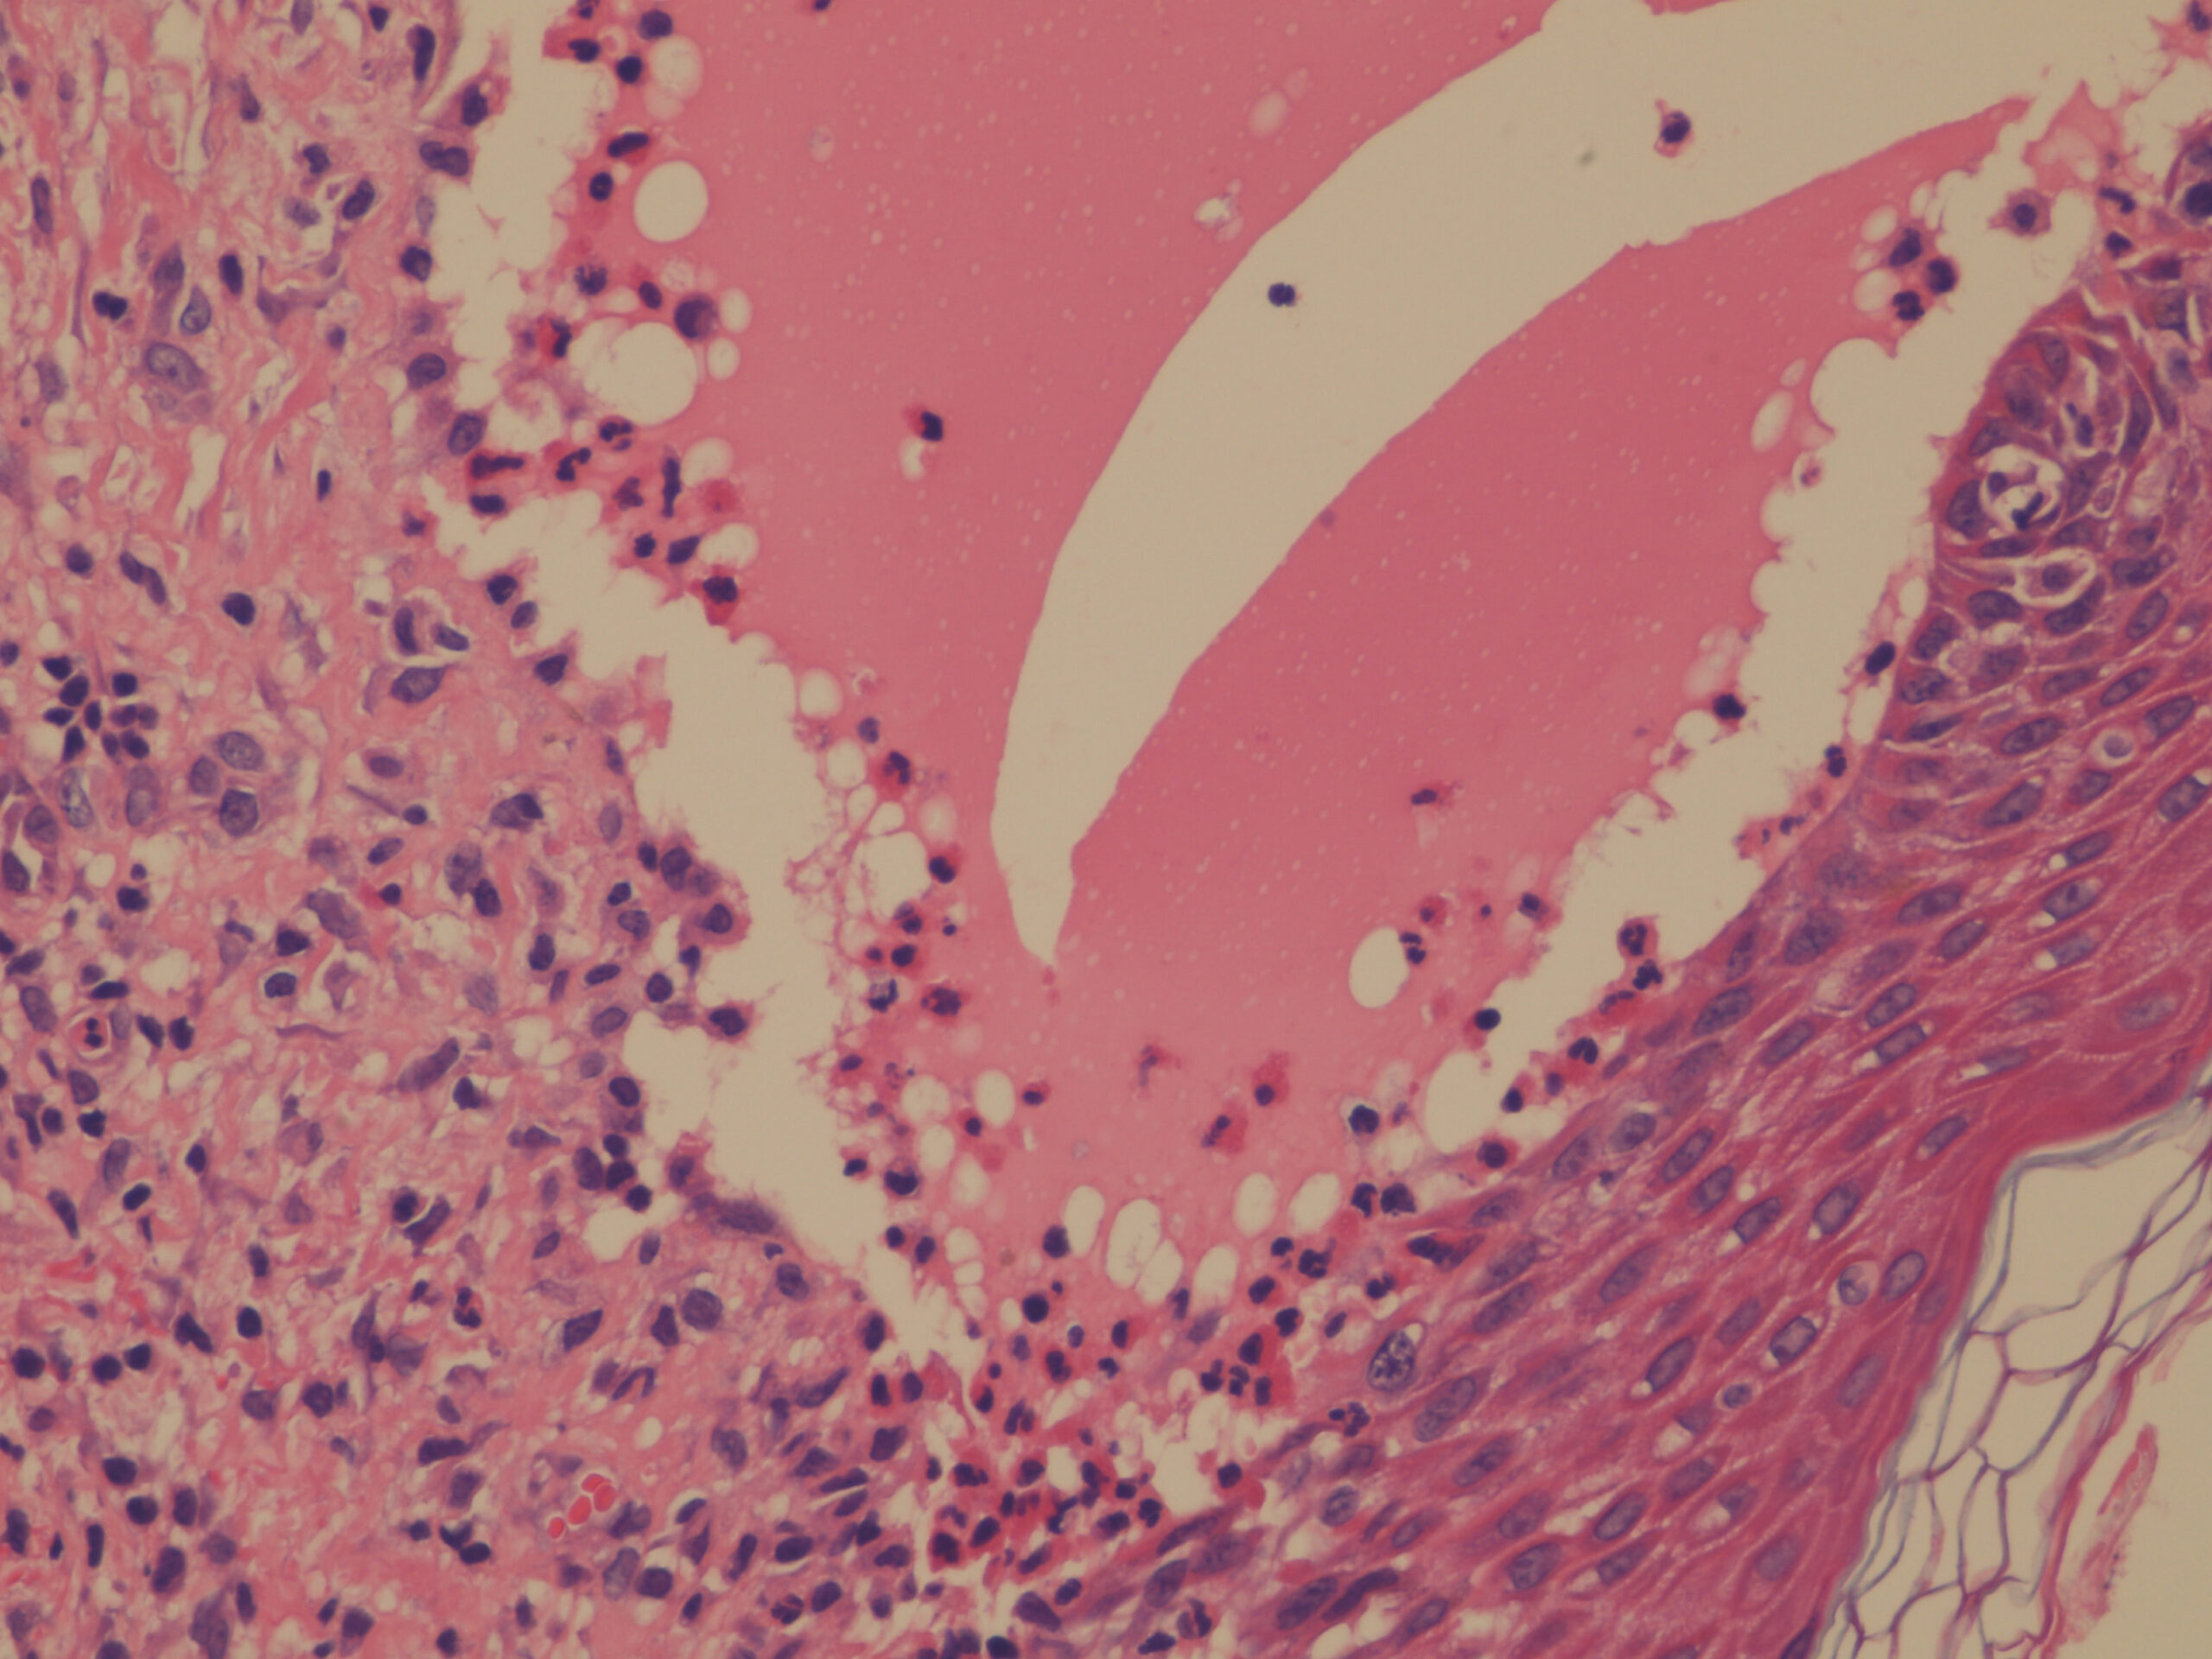

In early lesions, papillary dermal edema in combination with a cell-poor or cell-rich perivascular lymphocytic and eosinophilic infiltrate is present. The blister arises at the dermal-epidermal junction . In the cell-rich pattern, which correlates clinically with blisters arising on erythematous skin , eosinophilic papillary abscesses may develop with numerous perivascular and interstitial eosinophils intermingled with lymphocytes and neutrophils in the superficial and deep dermis. Early lesions may have the histologic features of eosinophilic cellulitis (Well’s syndrome). Eosinophilic spongiosis may occur. The cell-poor pattem is observed

when blisters develop on relatively normal skin , in which there is usually a scant perivascular lymphocytic infiltrate with few eosinophils, some scattered throughout the dermis and others near the epidermis. The blister contains few inflammatory cells. Epithelial migration and regeneration may result in an intraepidermal split in older blisters. Similar to pemphigus vegetans, a hyperplasia of the epidermis, subepidermal bullae, and accumulations of eosinophils and lymphocytes may be seen.